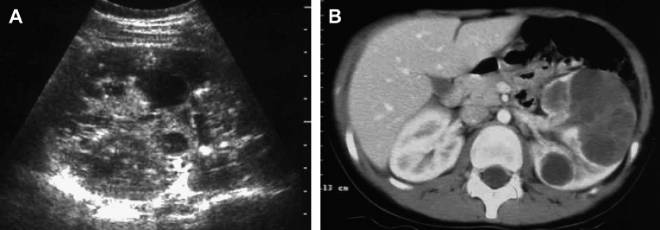

Паренхиматозная киста левой почки представляет собой доброкачественное образование, заполненное жидкостью, которое возникает в тканях почки. Врачи отмечают, что такие кисты могут быть бессимптомными и часто обнаруживаются случайно при ультразвуковом исследовании. Однако в некоторых случаях пациенты могут испытывать дискомфорт в области поясницы, а также боли, которые могут иррадиировать в бок или живот.

Киста паренхиматозного типа протекает бессимптомно и даже в процессе увеличения в размерах практически никак не проявляется. Паренхиматозная киста почки что это такое с точки зрения симптомов? На запущенных стадиях роста и развития почечной кисты больной человек может ощущать тянущие боли в пояснице или внизу живота, а также общую слабость и дискомфорт в боку, где находится поврежденный орган. Однако все эти первичные симптомы люди с кистой часто принимают за возрастные изменения и последствия заболеваний органов тазового пояса: защемление седалищного нерва, усталость от физических нагрузок, воспаление мочеполовой системы, воспаление мочеточных каналов, межпозвоночную грыжу.

При выявлении малейших симптомов заболевания, а также при появлении признаков проблем с мочеполовой системой, больной обязан немедленно обратиться к доктору. Врач назначит необходимое обследование, УЗ-сканирование органов брюшной полости и определит оптимальное лечение кисты паренхимы правой почки или левой стороны органа.